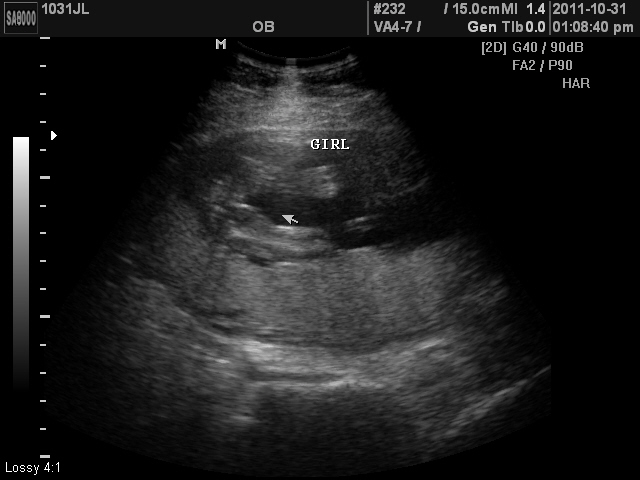

Alrighty all! Sorry its been so long. We have been able to find out what we are having. :) Its a GIRL! So happy!

Here are some pictures of our little Marilyn Mae